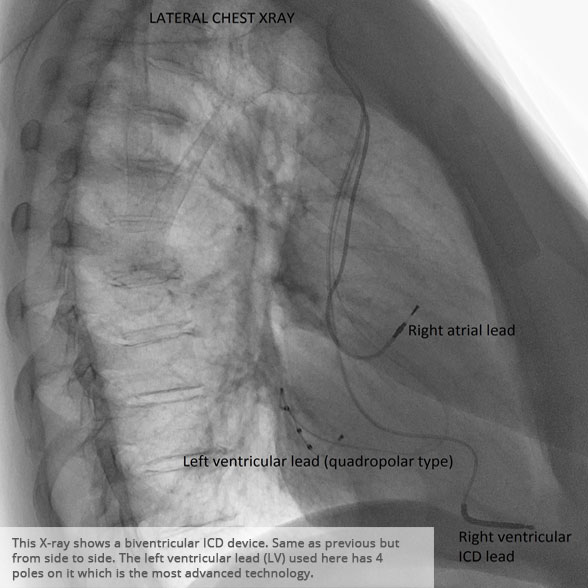

Lateral chest x-ray 1 Lateral chest x-ray 1

Lateral chest x-ray 2 Lateral chest x-ray 2

Above: Slideshow containing X-rays of common medical procedures.

BI-VENTRICULAR PACEMAKERS

Bi-ventricular pacemakers are used for the treatment of suitable patients with heart failure who are already on medication but who suffer from a lack of synchrony between the right and left ventricular contraction. This is most commonly caused by an electrical delay (left bundle branch block LBBB) in transmission of signals to the main pumping chamber (called the left ventricle) and is relatively common in patients with advanced heart failure. This delay process commonly worsens the symptoms of heart failure and it is not generally influenced by medication alone.

Although not all patients universally respond to bi-ventricular pacing (or cardiac resynchronisation therapy/CRT), patients with more advanced dys-synchrony tend to experience remarkable improvement. Bi-ventricular ICDs have the additional benefit of recognising life threatening arrhythmia and deliver both fast pacing bursts or shocks to restore normal heart rhythm.